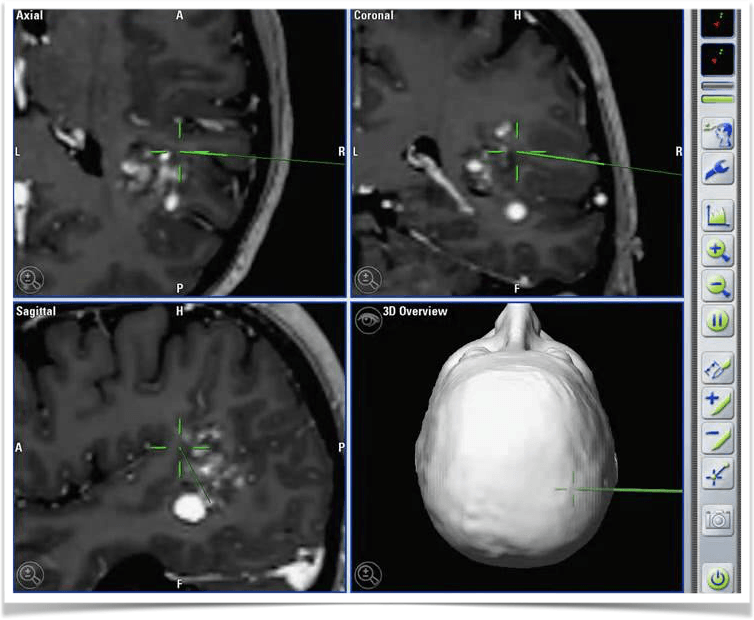

Neuronavigation is an essential surgical support tool in Neurosurgery. Using an optical or electromagnetic facial recognition software and system, the navigator is capable of locating any intracranial injury in space, and we are able to "see" through the skull.

This tool allows for smaller incision and less agression to the brain.